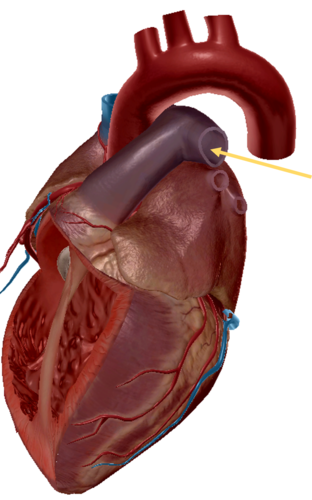

aorta

aortic trunk

pulmonary semi-lunar valve

pulmonary trunk

aortic trunk

aortic semi lunar valve